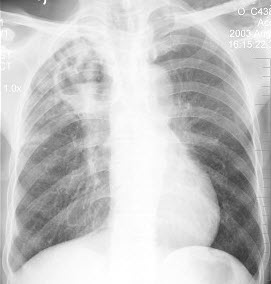

134、单项选择题

男,52岁,从事矿井工作32年,近几年出现气喘,呼吸困难,胸片如图,其最可能的诊断为()

A.双肺浸润性结核

B.双肺真菌感染

C.两肺弥漫性间质性肺炎

D.两肺弥漫性纤维化

E.矽肺

135、判断题 先天性髋内翻一般出生时即有典型的X线改变。